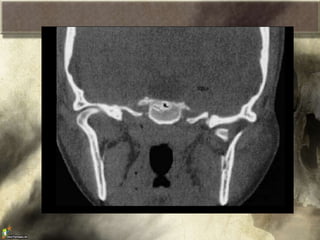

Fracturas Orbitaria

• La compresion del ojo hace que aumente la

presion intraorbitaria dañando las zonas mas

débiles: el piso y la pared medial

Signos y sintomas:

– Edema periorbitario

– Equimosis periorbitario

– Hemorragia subconjuntival

– Diplopia

– Enoftalmos

– Escalones o irregularidades del reborde orbitario.

- Ptosis

- Proptosis

- Limitación de movimiento ocular

- Hemorragia subconjuntival

Fracturas Orbitaria • Lacompresion del ojo hace que aumente la presion intraorbitaria dañando las zonas mas débiles: el piso y la pared medial

Signos y sintomas: –Edema periorbitario – Equimosis periorbitario – Hemorragia subconjuntival – Diplopia – Enoftalmos – Escalones o irregularidades del reborde orbitario. - Ptosis - Proptosis - Limitación de movimiento ocular - Hemorragia subconjuntival